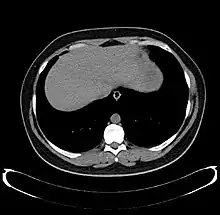

CT scan showing an adult liver in the axial plane

Organogenesis, the development of the organs, takes place from the third to the eighth week during embryogenesis. The origins of the liver lie in both the ventral portion of the foregut endoderm (endoderm being one of the three embryonic germ layers) and the constituents of the adjacent septum transversum mesenchyme. In the human embryo, the hepatic diverticulum is the tube of endoderm that extends out from the foregut into the surrounding mesenchyme. The mesenchyme of septum transversum induces this endoderm to proliferate, to branch, and to form the glandular epithelium of the liver. A portion of the hepatic diverticulum (that region closest to the digestive tube) continues to function as the drainage duct of the liver, and a branch from this duct produces the gallbladder.[35] Besides signals from the septum transversum mesenchyme, fibroblast growth factor from the developing heart also contributes to hepatic competence, along with retinoic acid emanating from the lateral plate mesoderm. The hepatic endodermal cells undergo a morphological transition from columnar to pseudostratified resulting in thickening into the early liver bud. Their expansion forms a population of the bipotential hepatoblasts.[36] Hepatic stellate cells are derived from mesenchyme.[37]